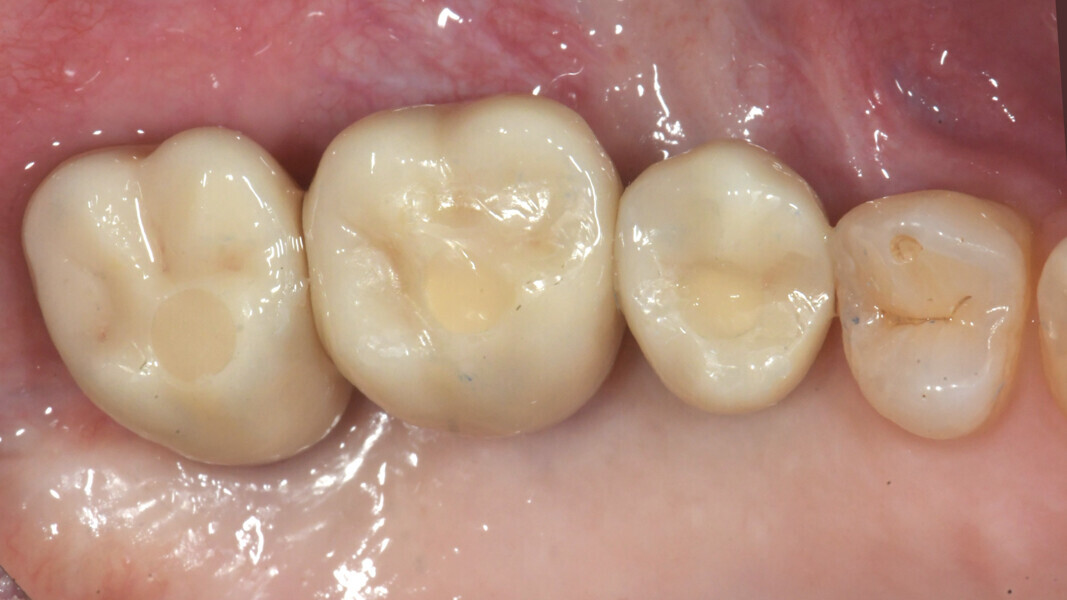

After three months, the implants were exposed through an apically positioned flap to increase the amount of keratinised tissue on the vestibular side of the implants and to realign the mucogingival junction, previously shifted towards the palate. Flared healing screws were placed to promote proper transmucosal healing. After one month, single ceramic crowns were placed for the first functional loading and temporary restoration while waiting for complete bone maturation (Fig. 34). After six months, the crowns were replaced with zirconia crowns for the final functional loading and the definitive restoration (Figs. 35–38). Clinical and radiographic follow-ups at the first functional loading, at six months, 12 months and 24 months showed the health of the peri-implant tissue and the maintenance of peri-implant bone levels (Figs. 39a-d).